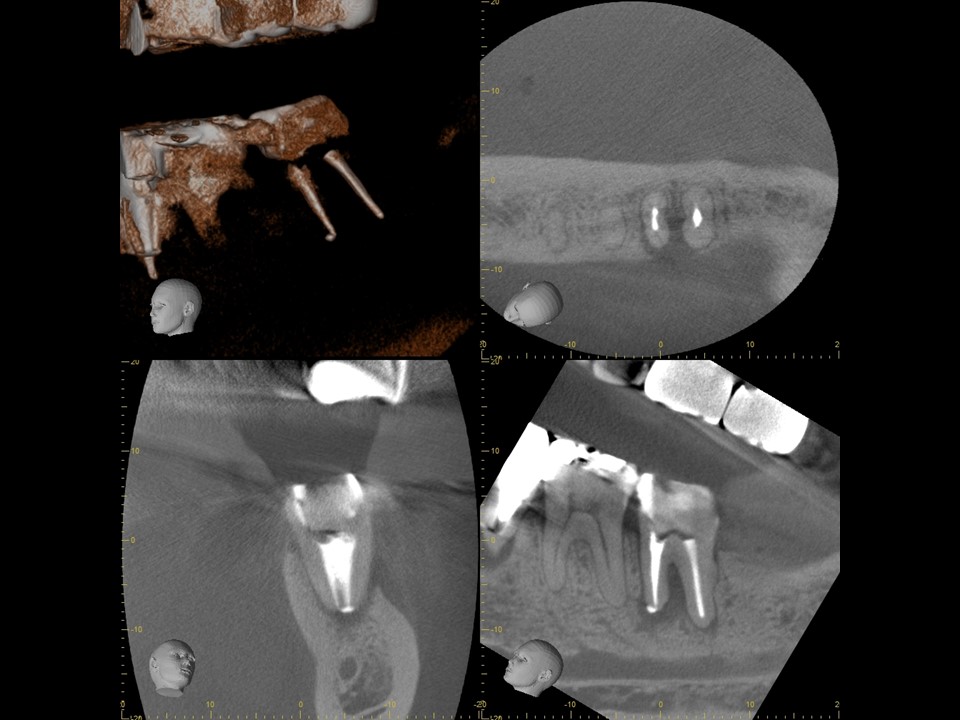

診断と治療計画の立案

当該の左下7番の奥歯はクラウンで被せてありましたが、頬側に歯茎の腫れ(フィステル、サイナストラクト)を認めました。レントゲンおよびCTによる診査を行ったところ、すでに根管治療が施してあるものの根管充填が不十分で、根尖病変を生じていました(下写真)。また、歯根の先端部分にはファイルと思われる器具の破折片を認めました(矢印)。根管内部へのバクテリアの感染による慢性化膿性根尖性歯周炎と診断し、再根管治療をおこなうことにしました。

治療前のレントゲンおよびCT画像です。当該歯はすでに根管治療が施してあり、根尖部には根尖病変によるX線透過像を認めます。

また、根尖部にはファイルと思われる器具の残存を認めます(矢印)。